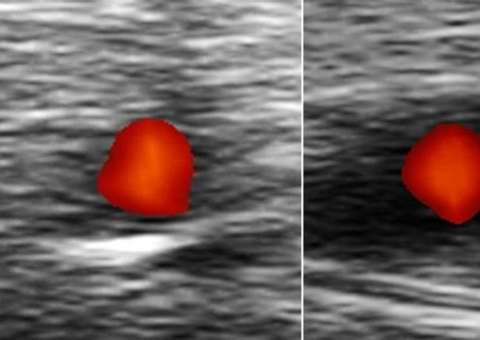

De acordo com o 'G1 Bem Estar’, o estudo avaliou amostras de sangue de 412 mãe de filhos diagnosticados com autismo e de 463 mães de filhos sem autismo. As amostras foram coletadas na 18ª semana de gravidez e durante o parto.